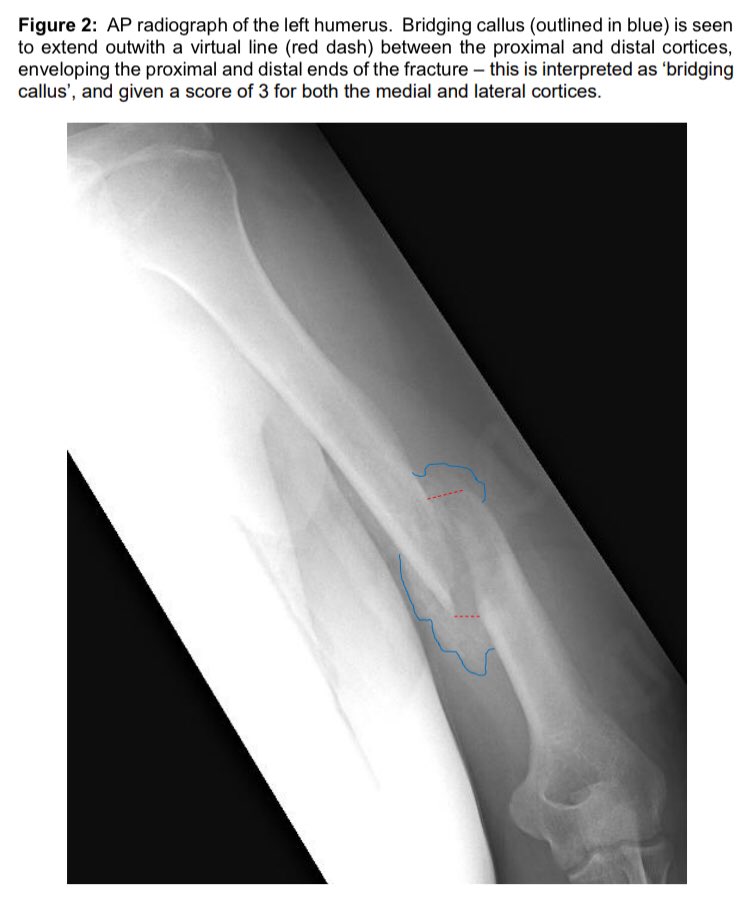

Also in this month’s

@BoneJointJ: The RUSHU can be used to assess healing & predict#nonunion at just 6 weeks after a non-operatively managed humeral shaft#fracture... Try it out in your next outpatient clinic! Full paper here: https://online.boneandjoint.org.uk/doi/full/10.1302/0301-620X.101B10.BJJ-2019-0304.R1 …pic.twitter.com/B1kzpOLGRI